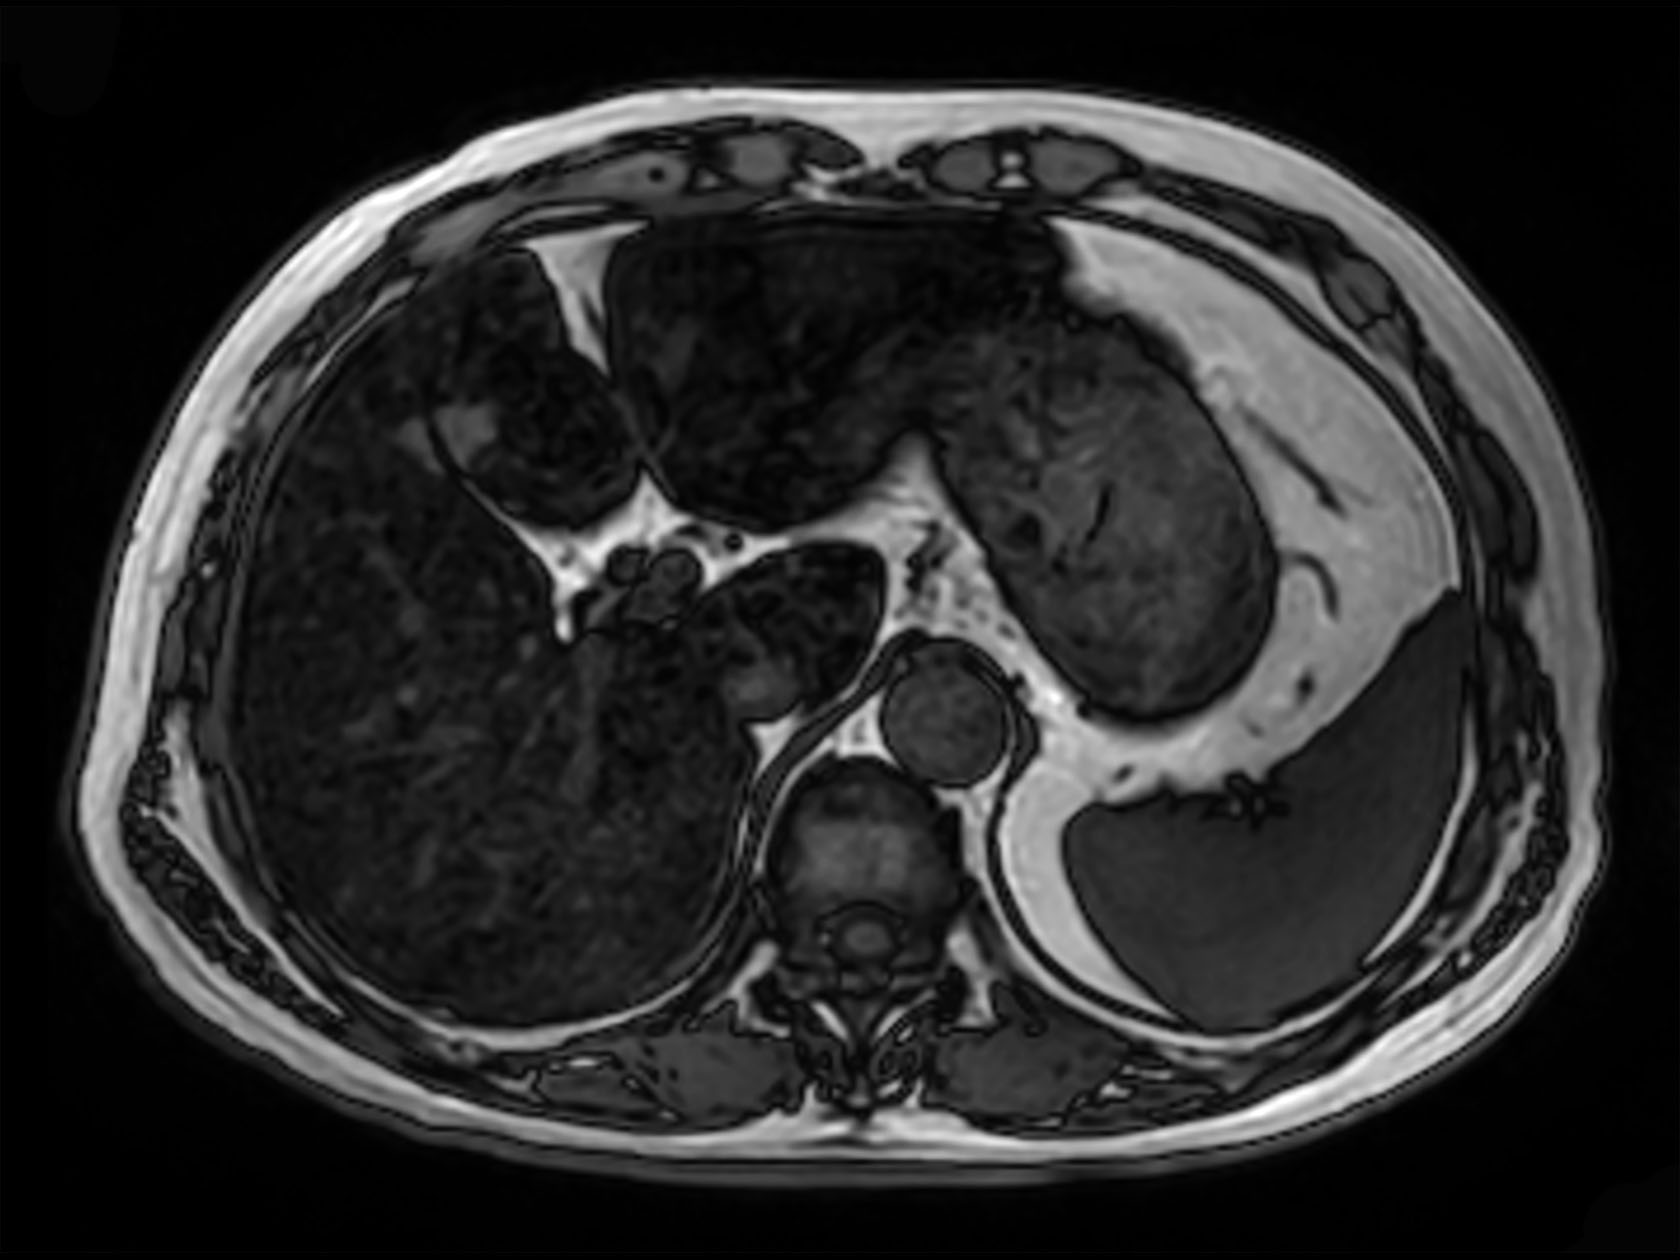

Axial mDIXON XD FFE (Out Phase)